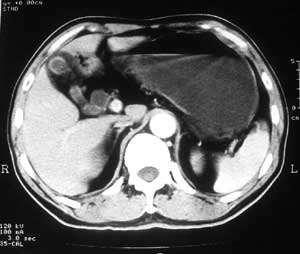

患者,男,57岁,梗阻性黄疸10余天。

这个病例胰头无明显增大,胆总管扩张明显而肝内胆管扩张更不明显,病程较短,

注意到十二指肠乳头明显突出,但尚光滑。分析以下可能性:

1、十二指肠乳头本身的病变,如乳头炎症;

2、急性乳头水肿,胆总管下端结石排石后乳头水肿;

3、壶腹部胆总管下端肿瘤累及十二指肠乳头。

十二指肠乳头粘膜慢性非特异性炎症